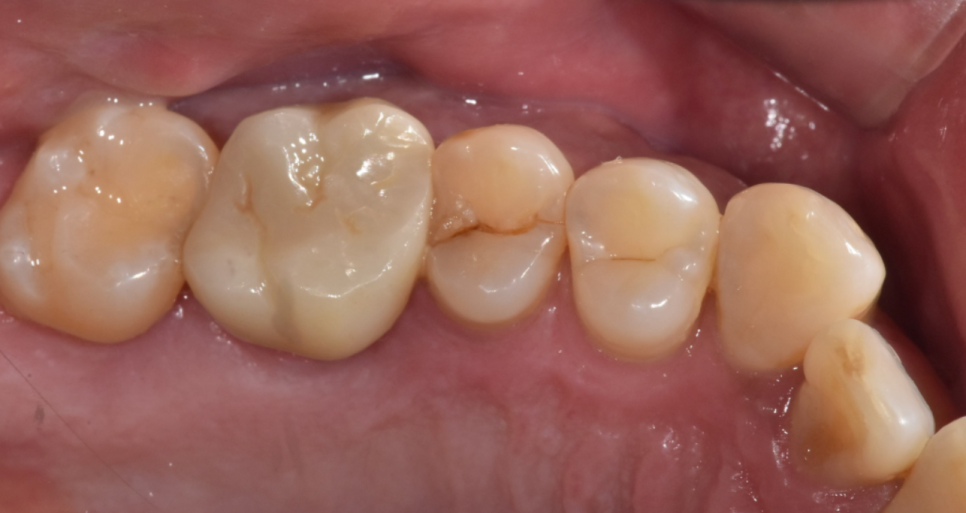

문제의 오른쪽 윗부분을 보는데..

딱 보입니다.

어금니 쪼개짐이 보입니다.

정확히 절반으로 어금니 쪼개짐

발생했습니다.

확대해서 보면

이런 모습이죠

환자분 혹시 딱딱한거 드셨나요~?

오돌뼈를 드셨답니다.